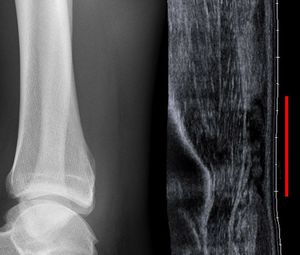

- Clinical diagnosis

- Ultrasound can be used in equivocal cases

- Comparing to normal ankle can reveal smaller defects or tears